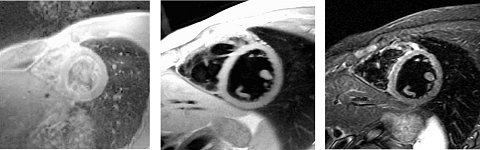

Figure 1. FSE (left), Double IR (center), and Triple IR (right)

Blood Suppression uses an inversion recovery preparation pulse that nulls signal from blood to obtain “black blood” cardiac images and reduce flow-related ghosting. This sequence can also be used to visualize cardiac anatomy, myocardial wall masses, and valve leaflets.

The terms Double IR FSE or Double IR SSFSE and Triple IR FSE or Triple IR SSFSE-IR are often used to refer to FSE or SSFSE with Blood Suppression and FSE-IR or SSFSE-IR with Blood Suppression, respectively.